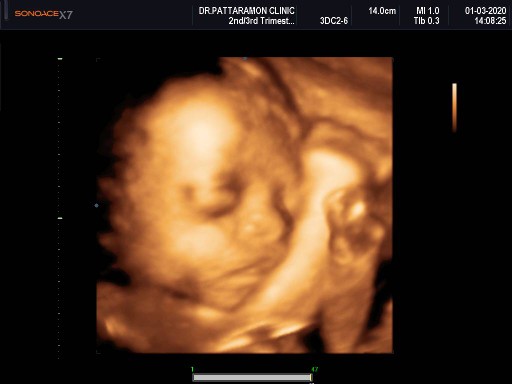

ซาวตอน 26+2 คะ